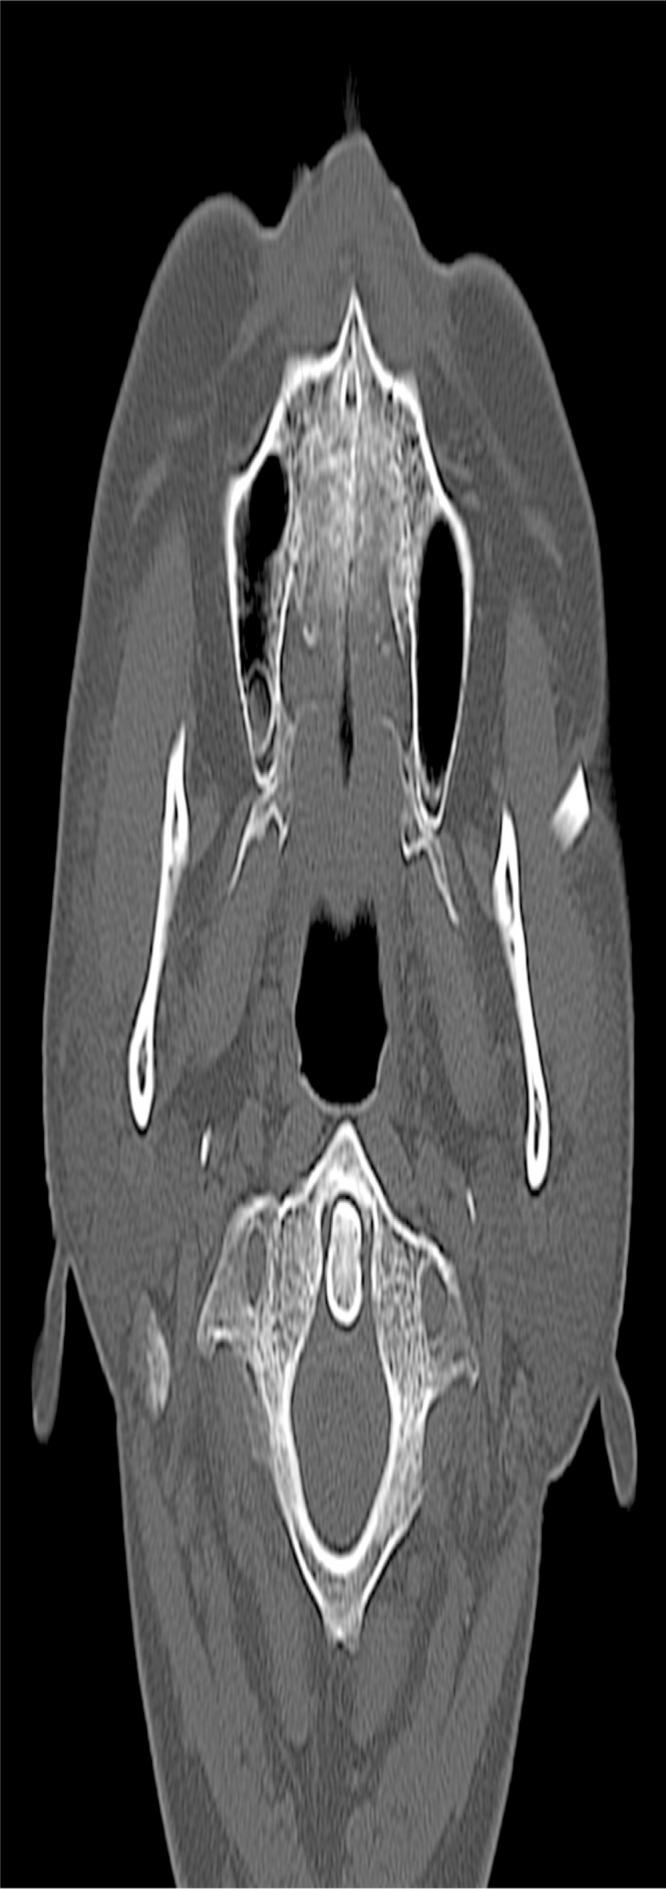

Foreign body (FB) impaction in the maxillofacial area could be caused by knives, glass fragments, and vegetative materials. We present the rare case of a 62-year-old man with a large glass FB in the left cheek retained for over 40 years. He had traffic accident over 40 years ago and glass fragments impacted on his left cheek. Glass fragments were retained around the zygomatic arch with dimpled scar and unclear serous discharge, but other facial motor or sensory dysfunction was not observed. We confirmed three glass fragments with radiologic examination including plain radiograph and computed tomographic image. Under general anesthesia, impacted glass fragments were removed through the direct incision on the dimpled scar and the additional incision on the left lateral canthal area. Remnant FBs were not seen on an intraoperative C-arm radiograph. After 2 days of irrigation for inflammation control, the dimpled wound was sutured. The wound was healed without major complication and the original dimpled scar was much improved.

摘要

异物(FB)嵌顿于颌面区域可由刀、玻璃碎片和植物性物质引起。我们报告一例罕见病例,一名62岁男性,左侧脸颊有一个大的玻璃异物,已留存40多年。40多年前他发生了交通事故,玻璃碎片嵌顿在他的左侧脸颊。玻璃碎片留存于颧弓周围,有酒窝状瘢痕且有不明浆液性分泌物,但未观察到其他面部运动或感觉功能障碍。我们通过包括X线平片和计算机断层扫描图像在内的放射学检查确认了三块玻璃碎片。在全身麻醉下,通过酒窝状瘢痕处的直接切口和左侧内眦区域的附加切口取出嵌顿的玻璃碎片。术中C形臂X线片未见残留异物。在进行2天的冲洗以控制炎症后,缝合酒窝状伤口。伤口愈合良好,无重大并发症,原来的酒窝状瘢痕明显改善。